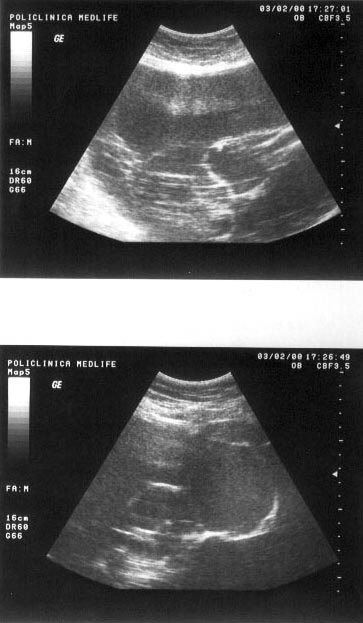

Imaginea transsonica

Structurile lichidiene (sangele, bila, secretiile digestive, continutul chistelor, ascita, colectia pleurala) sunt strabatute de catre ultrasunete in totalitate, fara a exista nici un fel de reflexii pe traseul acestora. Imaginea ecografica, fiind expresia unei "lipse de ecouri", va avea aspectul opus structurilor ecogene, respectiv culoarea neagra. O structura lichidiana este definita in ecografie prin termenul de transsonic.

Exemple:

structuri transsonice normale: colecist, vezica urinara, lumen vascular;

structuri transsonice patologice: chistul, continutul necrozat al unui abces sau al unei tumori maligne.

Figura 1. Vezica urinara

Figura 2. Chist renal stang situat in treimea medie

Figura 3. Chist ovar drept

Figura 4. Chist hepatic